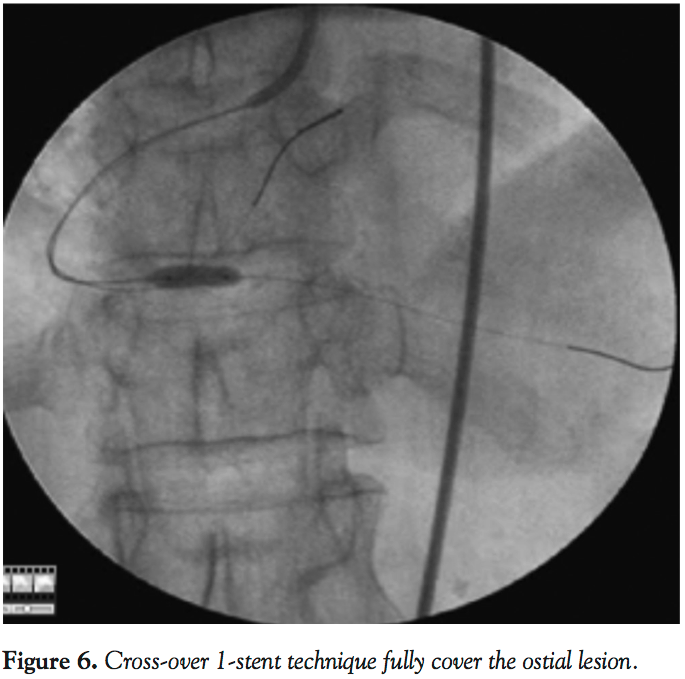

F. Cross-over 1-stent technique. This is the simplest technique when a stent is placed in the side branch and comes back into the main vessel (Figure 6). However, it leads to the risk of plaque shift from the carina into the main vessel. If the proximal vessel is much larger than the side branch, this mis-match can lead to stent malaposition in the main vessel. Optimization of the proximal portion of the stent often requires the use of a larger-size balloon. Occasionally, final kissing balloon inflations may be required to correct carina shift. If a dissection proximal to the stent occurs, then the procedure is shifted to a culotte two-stent procedure.

We have highlighted several techniques used to position stents accurately in ostial lesions. However, no perfect technique or technologies allow for perfect ostial stent placement in 100% of cases. New dedicated bifurcation stent technology may not be clinically available for several more years. Currently, aorta-ostial lesions are easiest to approach using the aorta floating-wire technique. For a Medina 001 lesion, the crossover 1-stent technique seems to be the quickest and easiest method, to allow for safe full coverage of the ostium. The Szabo technique should be reserved for well-experienced operators with careful lesion selection and preparation.